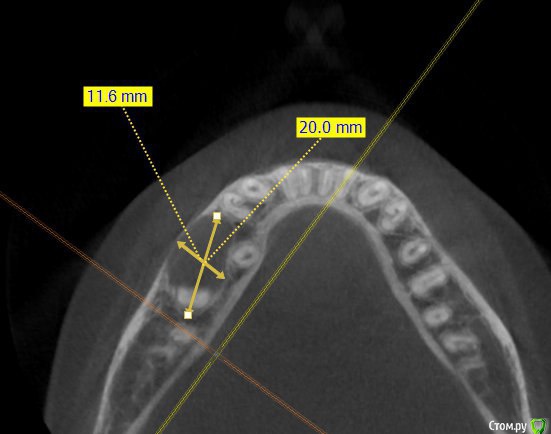

Kovalov Igor Опубликовано 14 июля, 2015 Поделиться Опубликовано 14 июля, 2015 (изменено) Уважаемые коллеги приветствую Вас! Встал вопрос стоит ли трогать фолликулярную кисту или наблюдать?Пациентка моя сестра, фолликулярная киста была случайной находкой, обнаружил ортодонт, отправил в областную больницу г. БелгородаВ детской ЧЛХ отказались, отправили в Харьков, это был 2013 год ещё. Во взрослой ЧЛХ не взялись, по возрасту. В детской члх сделали КТ, снимки и панораму прилагаю.Ps: картина за 2 года стала получше, но КТ сделают позже, есть внеротовой Rg снимок. Дело в том что я живу от сестры более 3000 км., сам бы это дело вскрыл амбулаторно, цистэктомия, графт+мембрана если гноя не будет... либо под йодоформом. Но вопрос стоит ли? и как по протоколу, каков Ваш план лечения? Депульпировать ли зубы 45-46? Изменено 14 июля, 2015 пользователем Kovalov Igor Ссылка на комментарий

Kovalov Igor Опубликовано 14 июля, 2015 Автор Поделиться Опубликовано 14 июля, 2015 вот Rg свежий. Вроде граница фолликулярной кисты уменьшилась.Как сделают КТ поделюсь тут... Буду признателен за ответы! Ссылка на комментарий

kriokov Опубликовано 14 июля, 2015 Поделиться Опубликовано 14 июля, 2015 Игорь' это не фолликулярная киста. Никакие зубы не депульпируйте. Сделате кт повторно. Сравните с прежними.скорее всего киста от ранее находившегося в дуге молочного зуба. После повторного кт можно будет сказать поточнее. Ну и с тактикой определиться. Сейчас что Вашу сестру беспокоит (жалобы)? 2 Ссылка на комментарий

Kovalov Igor Опубликовано 14 июля, 2015 Автор Поделиться Опубликовано 14 июля, 2015 Игорь' это не фолликулярная киста. Никакие зубы не депульпируйте. Сделате кт повторно. Сравните с прежними.скорее всего киста от ранее находившегося в дуге молочного зуба. После повторного кт можно будет сказать поточнее. Ну и с тактикой определиться. Сейчас что Вашу сестру беспокоит (жалобы)?А как отличит по КТ фоликулярную кисту от обычной кисты?Жалоб никаких не было, в 4 года ей лечили временный зуб в этой области. Возможно это и есть отголоски. Повторное КТ уже порекомендовал ей. Сделают, выложу тут.Благодарю Вас за ответ! Ссылка на комментарий

Alexey Doc Опубликовано 14 июля, 2015 Поделиться Опубликовано 14 июля, 2015 Фолликулярная киста связана с ( зачатком) зуба А как отличит по КТ фоликулярную кисту от обычной кисты?Жалоб никаких не было, в 4 года ей лечили временный зуб в этой области. Возможно это и есть отголоски. Повторное КТ уже порекомендовал ей. Сделают, выложу тут.Благодарю Вас за ответ! Фолликулярная киста связана с коронкой прорезывающегося или ретинированного зуба. А это скорее всего резидуальная 3 Ссылка на комментарий